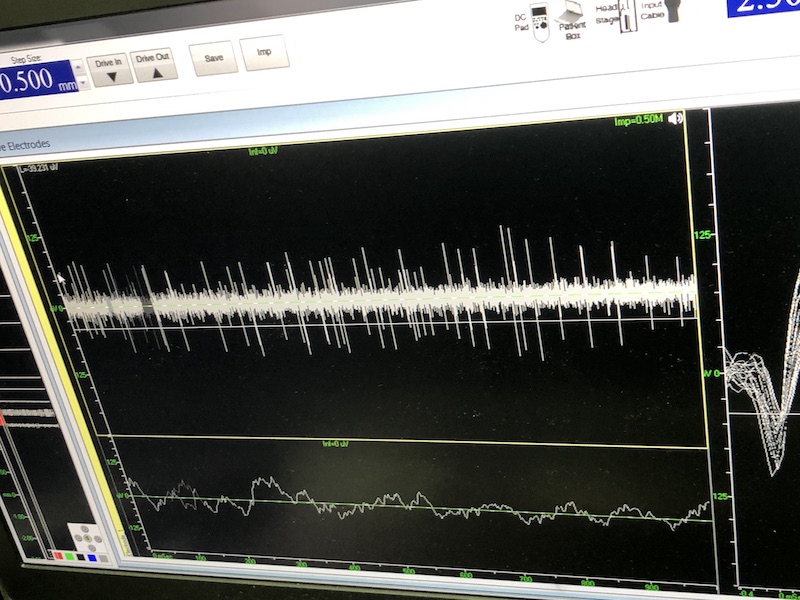

與此同時,檢測電極實(shí)時記錄電極末端每一點(diǎn)處的電信號,當(dāng)電極逐漸接近手術(shù)規(guī)劃靶點(diǎn)時,借助電信號的特征,醫(yī)生可以判斷電極是否已經(jīng)沿長軸植入患者顱內(nèi)的目標(biāo)核團(tuán),以及植入的準(zhǔn)確長度。下圖中,檢測信號屬于典型的核團(tuán)信號,證明電極已經(jīng)抵達(dá)相對理想的植入位置,記錄下此刻的位置后,即可在相應(yīng)位置植入刺激電極。

檢測核團(tuán)信號